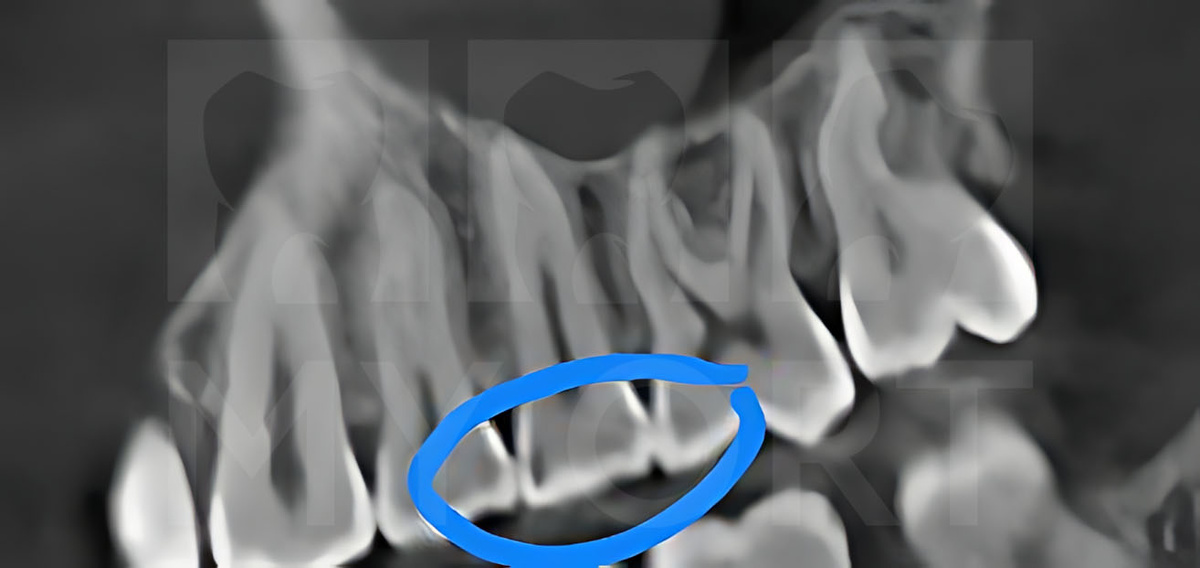

Для оценки состояния зубов и планирования ортодонтического лечения было проведена КЛКТ (конусно-лучевая компьютерная томография).

На снимках я обнаружила скрытые кариозные полости, не видимые при обычном визуальном осмотре.

Скрытые кариозные полости на снимке КЛКТ